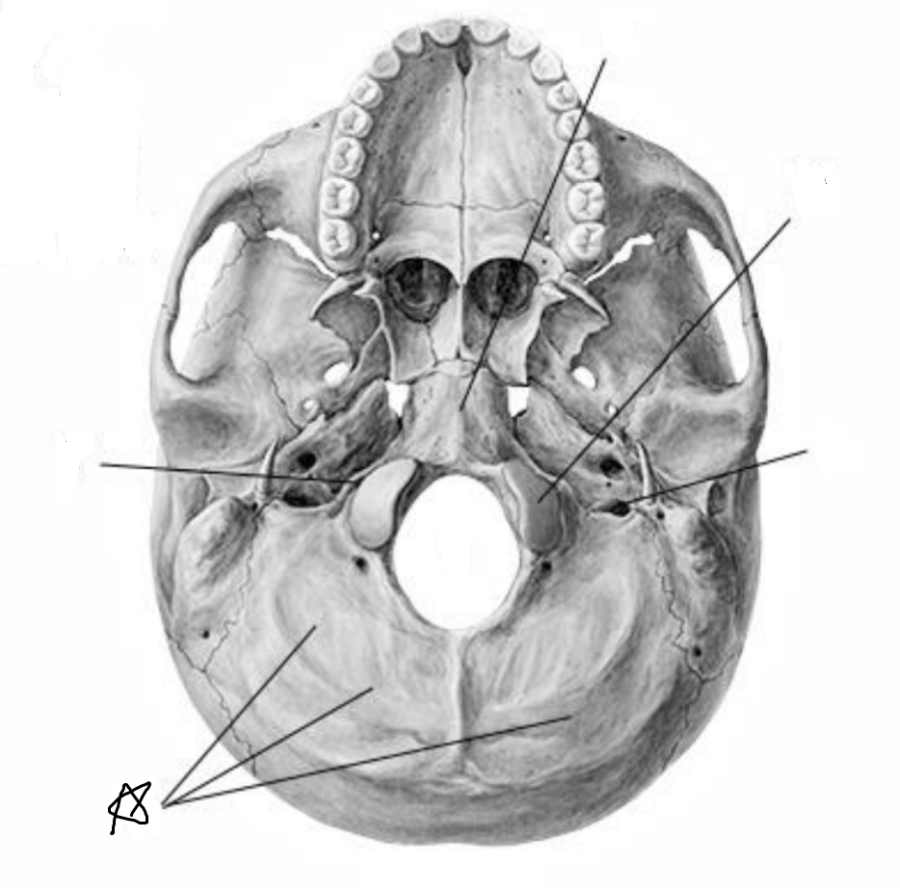

Анатомические детали: Фотографии топографии черепа с нижнего вида